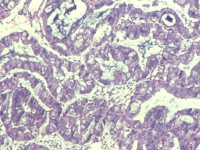

性别

女

年龄

55岁

临床诊断

异常子宫出血

一般病史

阴道不规则出血1月

标本名称

子宫内膜

大体所见

灰白色组织1堆、4*3.4*2.2CM大。

能诊断癌吗

图2

子宫内膜样腺癌

雾蒙蒙:

支持。